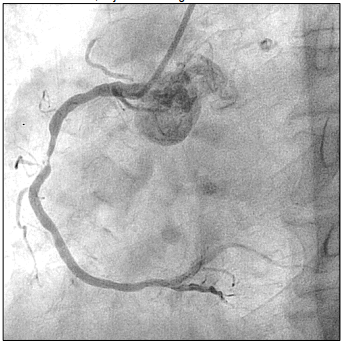

Paciente de 66 anos, relata queixa de dor torácica em aperto. Procura atendimento médico onde realiza ECG que evidencia IAM com supra de ST. Então, é levada à hemodinâmica onde é realizado o exame, cujo achado segue abaixo:

Enunciado 3103606-1

Em relação à anormalidade evidenciada, assinale a alternativa que apresenta a coronária acometida.